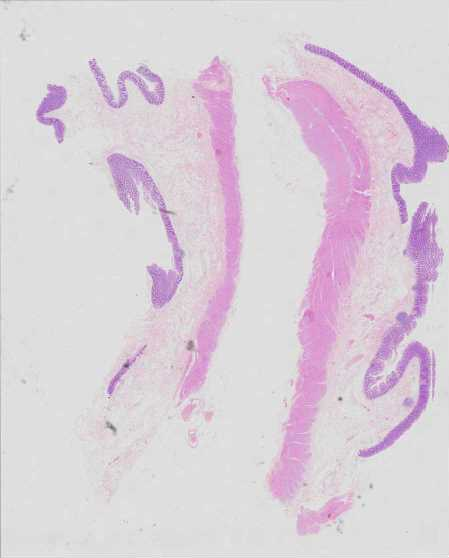

Use Case 1

2403668

Overview Statistics B details